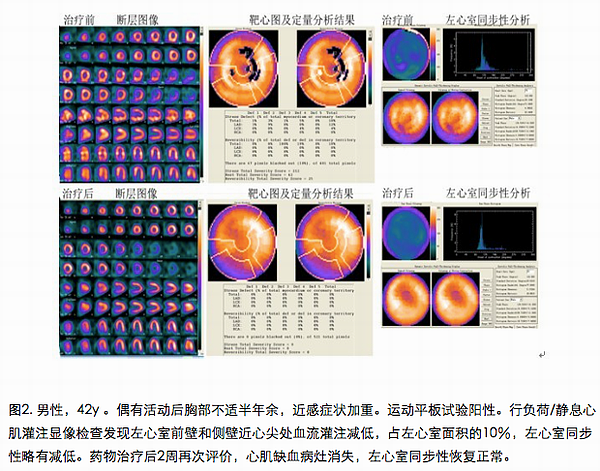

利用只有存活心肌才能够摄取葡萄糖的原理(换言之,die的心肌就算有血流供应,也不能显像;没有血流供应的心肌也可能因为alive而显像),借助特殊的处理软件可以获得存活心肌的分布图像及其他相关参数。通过与血流灌注图像进行对比,可以明确血供不足但是仍然具有活力的心肌的面积,从而预估冠心病患者再灌注治疗的获益价值;或与治疗前的图像对比,直观地反应心肌的恢复情况。